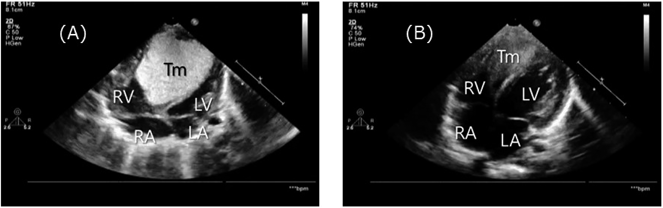

Fig. 3 Echocardiographic appearance

(A) At birth. The largest cardiac rhabdomyoma occupied most of the RV, size 36×30 mm. (B) Day90. The tumor significantly regressed. LA=left atrium; LV=left ventricle; RA=right atrium; RV=right ventricle; Tm=tumor.

出生時から動脈管血流が左右短絡優位であり,左室からの順行性血流で体循環は維持できていたため,PGE1投与は行わず,腫瘍の自然退縮を期待して注意深く経過観察することとした.日齢1の心エコー検査ではLVEDD 13.4 mm(対正常値比89%),EF 70%と肺血流増加による前負荷増大の影響と考えられる改善を認めた(Fig. 3A).また,肺血管抵抗低下に伴い日齢3に動脈管血流は左右短絡のみとなった.日齢5に動脈管の自然閉鎖を確認したが,明らかな循環動態の変化は認めなかった.フォローアップ目的で日齢10に,鎮静下に心臓MRIを施行した.しかし,日齢11に60/分以上の多呼吸と四肢冷感を認め,血液ガス分析で混合性アシドーシスを認めた.心エコー検査では壁運動の高度低下を認め,EF 15%であった.このときの血液検査で炎症反応の上昇は認めず各種培養検査も陰性,また心電図検査でも虚血性変化を認めなかった.腫瘍の圧迫自体が原因の重症心不全と考えられた.完全鎮静,挿管人工呼吸管理開始,また0.2 µg/kg/minでミルリノンの投与を開始した.治療開始後はEF 20%程度に上昇を認めたが効果は限定的であった.腫瘍自体への治療介入として,everolimusの投与を開始することとした.適応外使用となるため治験審査委員会の未承認薬申請審査を迅速に通し,両親への説明を行い,文書による同意を得た.また,everolimusの費用に関しては診療科負担とした.日齢19より,文献2)を参考にして1 mg/m2/day 分1で投与を開始した.目標トラフ値を5~15 ng/mLと設定,4回内服後,5回目内服直前のトラフ値を測定し用量を調節した.当初はトラフ値の十分な上昇が得られずこまめな増量を要したが,2.5 mg/m2/dayとしたところで目標トラフ値を超えるようになり,最終的には開始量である1 mg/m2/dayを維持量として退院時まで投与した.当初,腫瘍の最大径は36 mm,四腔断面像で計測した腫瘍断面積は1,000 mm2を超えていたが,Fig. 2に示すようにeverolimus開始後腫瘍サイズは縮小傾向となり,日齢35には496 mm2と半分以下にまで縮小した.腫瘍の縮小に伴い心機能も徐々に改善し,日齢42には抜管が可能であった.抜管後ミルリノンを0.1 µg/kg/minに減量するとともにピモベンダンを0.05 mg/kg/dayで内服開始,またカルベジロールの内服も0.02 mg/kg/dayと少量から開始した.カルベジロールは1週間ごとにおよそ倍量に増量し,日齢55からは0.1 mg/kg/dayとし,維持量とした.日齢60でミルリノンの投与を終了,日齢68よりピモベンダンを0.1 mg/kg/dayに増量した.その間腫瘍の再増大はなく,心機能も改善傾向であり,体重増加も得られるようになったことから,日齢93に退院とした.なお,退院時心エコー検査では,EF 54%にまで改善していた(Fig. 3B).